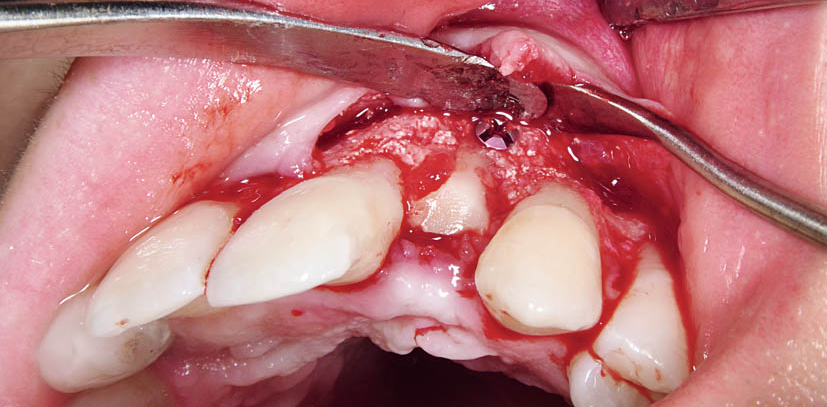

The implant in region 22 was explanted and the tissue sections modified by inflammation were carefully curetted. As suggested by the X-rays, the operation found a significant multiwalled bone defect (Figs. 2-3). Eight weeks after explantation, the defect region was augmented with an autologous bone block from the mandibular angle as well as bone substitute material (botiss cerabone®) and a collagen membrane (botiss Jason® membrane). Six months after bone augmentation, a one-piece diameter-reduced ceramic implant was implanted (diameter: 3.3/length: 10 mm). Because of the narrowness of the mesio-distal spaces in region 22, only a diameter-reduced implant could be used here. On the buccal side, autologous bone chips from the zygmomatic bone region were harvested (Figs. 4-5). The healing process was normal(Fig. 6). The implant was exposed to the oral cavity and healed without inflammation under the protection of the pre-­operatively fabricated temporary clamp prosthesis.